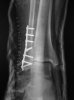

Mrsdrron had her surgery last night.5 hours and now has 9 screws and 2 plates in her ankle.

So check out this x-ray - check out 4th screw down - what's goin' on there? Might explain why so many people say 'I have a screw loose' !

I have plate and 7 screws in ankle and I just cannot set off security alerts - so disappointed - I wish mrs.dr.ron all the best.